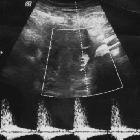

Ultrasound

Small focus of color signal on Doppler ultrasound with distinctive "to-and-fro" waveform at the neck of the pseudoaneurysm .